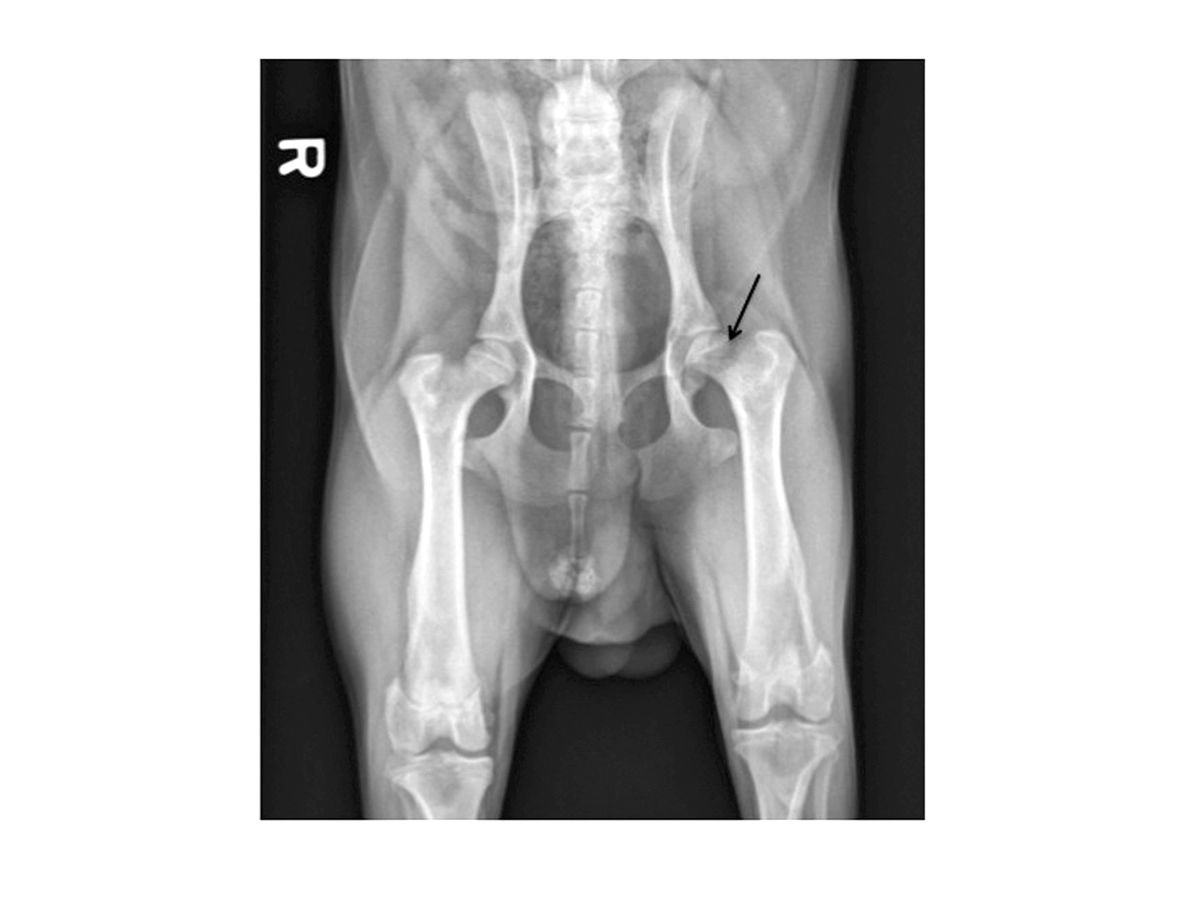

Aunque con la exploración física y la reseña del paciente se puede sospechar firmemente una ELCP, para poder confirmar el diagnóstico suele ser necesario el estudio radiológico. En las fases iniciales se pueden observar áreas de lisis y desmineralización en la región subcondral de la cabeza y cuello del fémur (Figura 1). A medida que la enfermedad avanza, puede evidenciarse el colapso de la cabeza y cuello femoral (Figura 2). Después, en fases más tardías, es posible observar la remineralización y la cicatrización ósea. También pueden presentarse alteraciones indicativas de una osteoartritis secundaria, que incluyen la formación de osteofitos (especialmente en el borde acetabular dorsal) y el aplanamiento de la cabeza femoral.

Esta radiografía muestra alteraciones moderadas de la ELCP. La flecha indica la pérdida significativa de hueso subcondral y del cuello femoral, con remodelación de la cabeza femoral.

Figura 2. Esta radiografía muestra alteraciones moderadas de la ELCP. La flecha indica la pérdida significativa de hueso subcondral y del cuello femoral, con remodelación de la cabeza femoral.© Darryl L. Millis